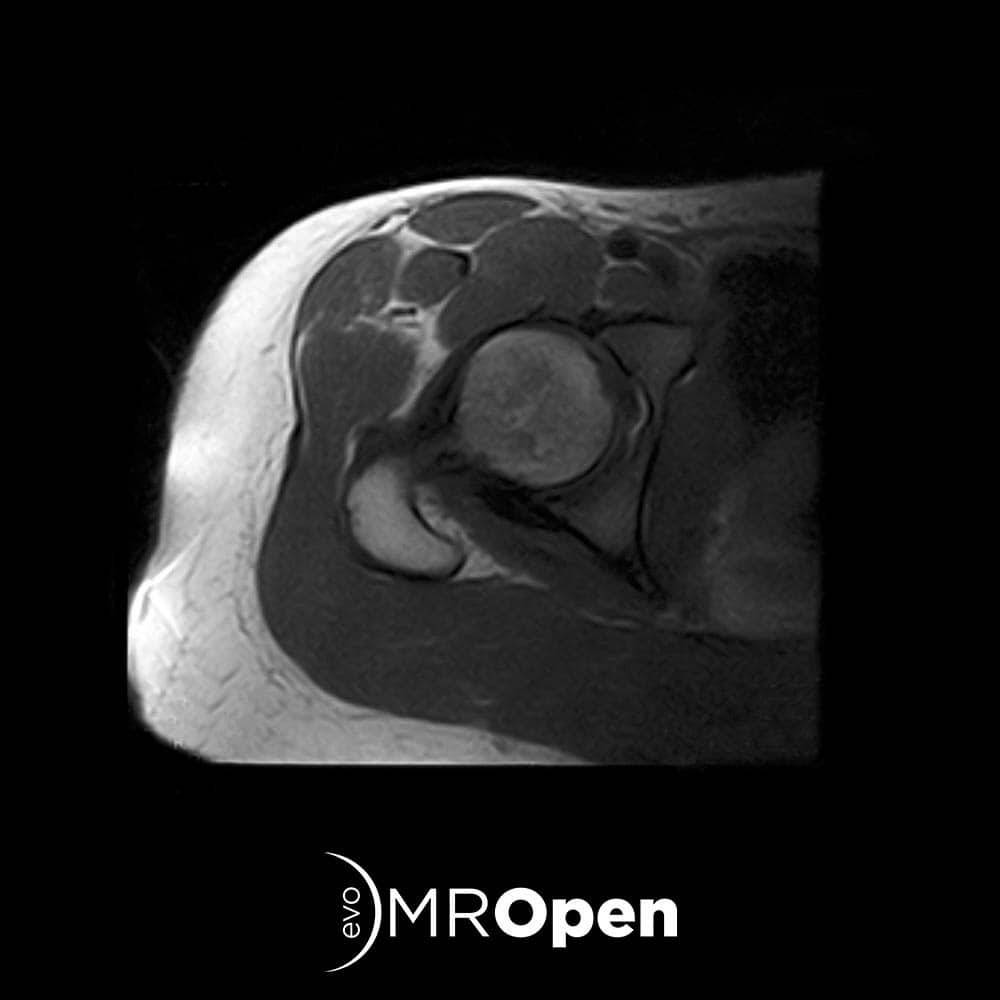

EVERYDAY LIFE

With MROpen Evo you can achieve all the standard MRI procedures for MSK and Neuro imaging. Thanks to a complete set of anatomy-dedicated receiving coils and customized examination protocols setup, your normal daily routine is completely covered, with optimized workflow, high level image quality and unique patient comfort.

To cover specific needs, differentiate your offer and increase the total number of patients MROpen Evo is a perfect choice for your centre as a stand alone scanner or associated with a traditional MRI.